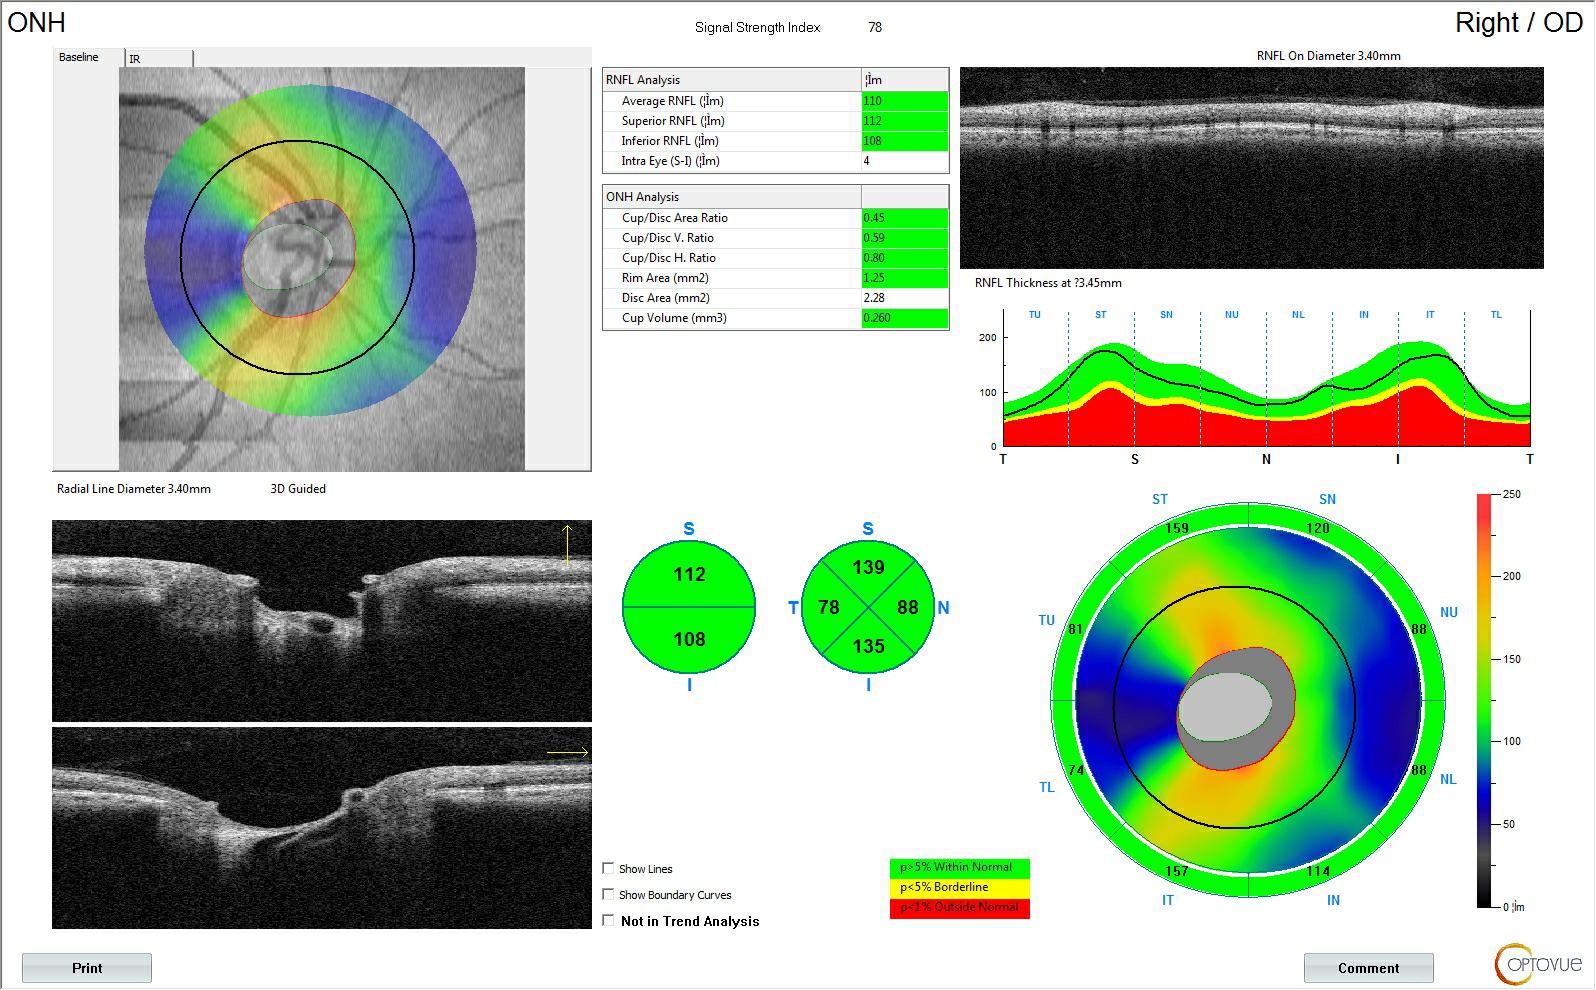

5、青光眼患者早期随访:监测青光眼盘内及盘周血流。

监测青光眼盘内及盘周血流